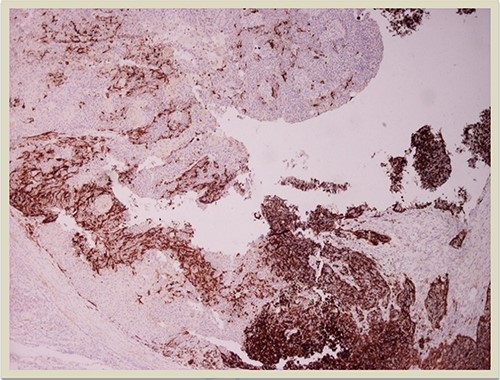

A 69-year-old man was admitted to our hospital with a nodular skin tumor of the back (Fig. 1). The patient had no ongologic history. We performed excisional biopsy that revealed collision tumor. The collision tumor consisted of mixed melanosquamous tumor (dermal squamomelanocytic tumor) together with BCC (Fig. 2). The BCC was superficial spreading. The mixed element contained squamous cell carcinoma of well/moderately differentiated and a neoplasm with melanotic characteristics, which due to cell atypia, presence of mitoses and high index of cell proliferation (Ki67: 80%) was described as melanoma (Fig. 3). Diagnosis of the melanotic and the squamous element was confirmed with immunohistochemistry (Figs 4 and 5).

HMB45 × 4: HMB45 immunostain highlights the malignant melanocytic component ( ×10 magnification).

Histologically the collision tumor involves two different and distinct entities. There is no interaction between the tumor cells of the two different neoplasms. The paradox in our case is that the melanotic cells were admixed with squamous cells. The histopathologic findings of the combined tumor were confirmed with immunohistochemistry. Squamous element was confirmed from the positivity of the stains: AE1/AE3, EMA and CK5. Melanotic element was also confirmed with the following stains: Vimentin, S-100, MART-1(Melan-A) and HMB45. Histologic findings and immunohistochemical stains confirmed the combined melanosquamous neoplasm in the collision tumor, which does not seem to involve epidermis. Reviewing the literature, we did not find any other case of a combined neoplasm in a collision formation.